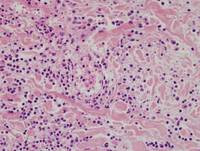

Category: Lymphoma: Mature T and NK cell lymphoproliferations > EBV+ T- and NK-cell lymphoproliferations > Chronic Active EBV Infection > Cutaneous Chronic Active EBV Infection > Hydroa Vacciniforme-like Lymphoproliferative Disorder